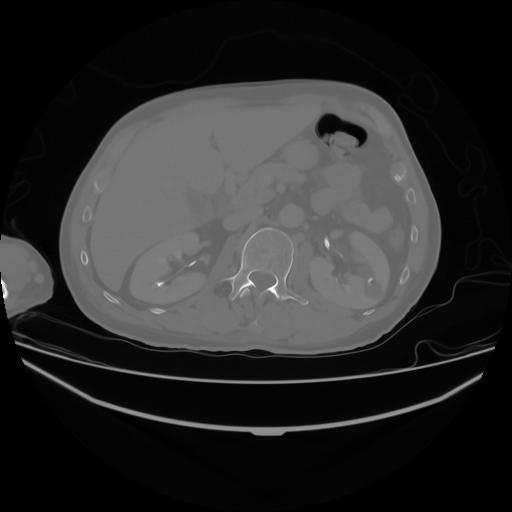

4 CUERPO,CE,Axial,3.0,CUERPO,,